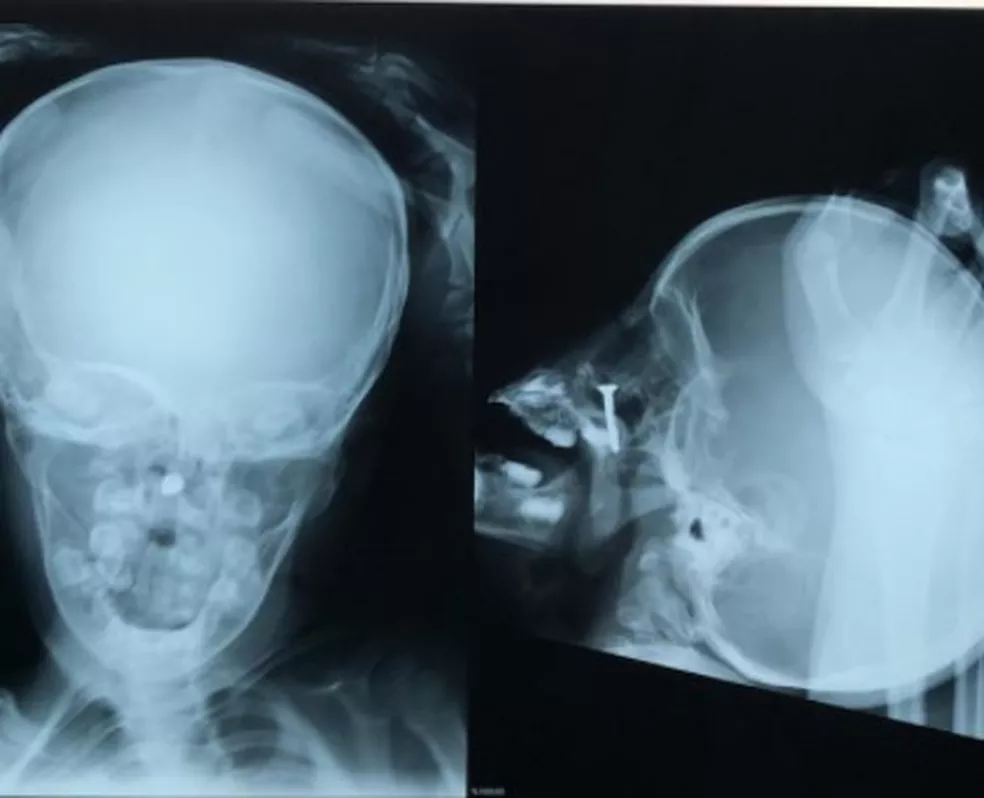

“Ela enfiou um parafuso dentro do nariz, a criança quando chegou estava muito agitada, tivemos que fazer uma radiografia para ver onde exatamente o objeto estava. Teve que ser feito um procedimento cirúrgico nela com anestesia geral. Ela foi intubada, porque, como é muito pequena, havia o risco de o parafuso machucar e ter sangramento, caso ela se mexesse. Então, optamos por esse procedimento por vídeo.”

Parafuso foi retirado de dentro do nariz de uma criança de dois anos — Foto: Arquivo pessoal